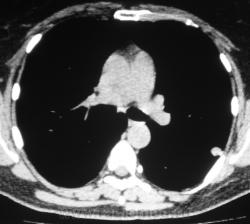

Произведена КТ.

КТ хотелось бы посмотреть в dicom-формате, меняя режимы, но на мой взгляд образование содержит известковые включения. Хотя, я не настаиваю, дождемся мнения коллег.

Нет "волшебных методов", можна поставить диф. ряд. Я бы дала такое заключение: хондрогамартрома, дифференцировать с туберкуломой, периферический рак менее вероятен. Можно жизнь прожить с гамартромой, а может озлиться в саркому. На практике был случай, когда лет 10 наблюдалась классическая скиалогически туберкулома, которая за полгода выросла и оказалась аденокарциномой. Таким образом, при любом раскладе, хирургическое лечение не является ошибкой, но решение об операции на легком должен принимать консилиум.

Дело не в желании, а в смысле. Что тут ещё можно сказать? На мой взгляд-мелкая, частично кальцинированная туберкулома.

Да, более туберкулёма.